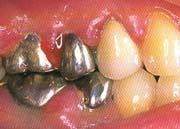

<インプラント治療>

<歯の中間で1本抜けた場合>

インプラント治療とは、歯の抜けたところに人工の歯根(インプラント)を植え、顎の骨としっかり固定させた後に、人工の歯を装着したものです。

これにより自分の歯のようにお肉やスルメを噛むことができるようになります。

※次のような患者様にインプラントは適しております。

・入れ歯が嫌いな方や入れ歯が合わず、痛みがある方など

・歯の抜けた場所を治療するのに隣の歯を削りたくない方

・以前と同じ天然歯のような歯が欲しい方 など